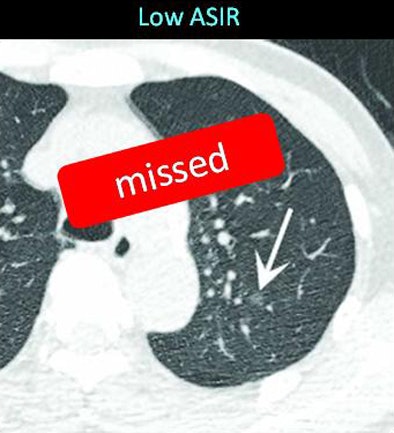

| The same ground-glass opacity (arrow) is visible on both MBIR (below) and ASIR (above) reconstructions in two different scans of the same patient, but it is fainter with ASIR and was missed by two radiologists evaluating the image. Images courtesy of Dr. Masaki Katsura. |